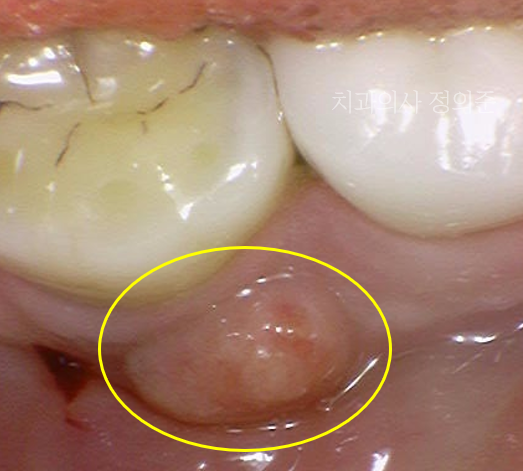

잇몸이 부어서 내원하셨을 때의 구강 내 사진 (2024. 3)

어느날, 잇몸이 붓고 너무 아프다고, 잇몸치료를 원하셔서 내원하셨습니다.

검진 결과 왼쪽 아래 첫번째 어금니 치아의 볼쪽으로 고름 주머니가 잡힌 것이 관찰되는데요.